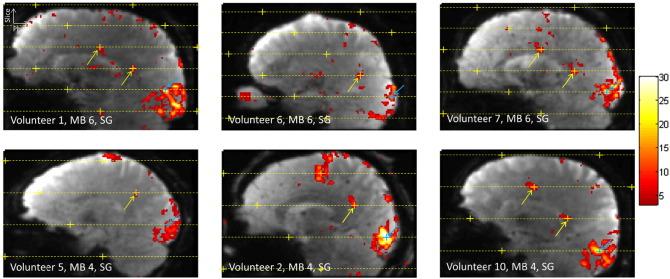

Functional magnetic resonance imaging (fMRI) studies that require high-resolution whole-brain coverage have long scan times that are primarily driven by the large number of thin slices acquired. Two-dimensional multiband echo-planar imaging (EPI) sequences accelerate the data acquisition along the slice direction and therefore represent an attractive approach to such studies by improving the temporal resolution without sacrificing spatial resolution. In this work, a 2D multiband EPI sequence was optimized for 1.5mm isotropic whole-brain acquisitions at 3T with 10 healthy volunteers imaged while performing simultaneous visual and motor tasks. The performance of the sequence was evaluated in terms of BOLD sensitivity and false-positive activation at multiband (MB) factors of 1, 2, 4, and 6, combined with in-plane GRAPPA acceleration of 2× (GRAPPA 2), and the two reconstruction approaches of Slice-GRAPPA and Split Slice-GRAPPA. Sensitivity results demonstrate significant gains in temporal signal-to-noise ratio (tSNR) and t-score statistics for MB 2, 4, and 6 compared to MB 1. The MB factor for optimal sensitivity varied depending on anatomical location and reconstruction method. When using Slice-GRAPPA reconstruction, evidence of false-positive activation due to signal leakage between simultaneously excited slices was seen in one instance, 35 instances, and 70 instances over the ten volunteers for the respective accelerations of MB 2×GRAPPA 2, MB 4×GRAPPA 2, and MB 6×GRAPPA 2. The use of Split Slice-GRAPPA reconstruction suppressed the prevalence of false positives significantly, to 1 instance, 5 instances, and 5 instances for the same respective acceleration factors. Imaging protocols using an acceleration factor of MB 2×GRAPPA 2 can be confidently used for high-resolution whole-brain imaging to improve BOLD sensitivity with very low probability for false-positive activation due to slice leakage. Imaging protocols using higher acceleration factors (MB 3 or MB 4×GRAPPA 2) can likely provide even greater gains in sensitivity but should be carefully optimized to minimize the possibility of false activations.